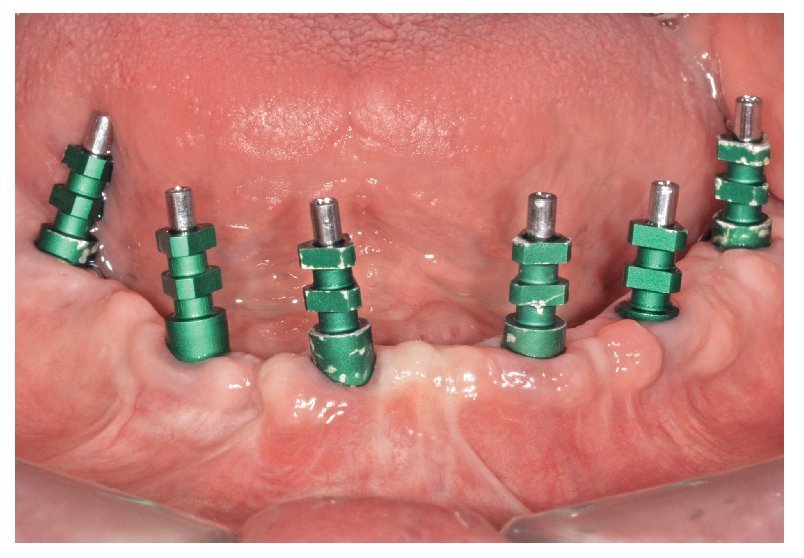

La intervención quirúrgica (figs. 63 y 64) se realizó bajo anestesia local y se trataron al mismo tiempo ambas arcadas dentarias. Durante la primera fase se insertaron seis implantes cónico-cilíndricos (SPI®CONTACT, Thommen Medical AG, Waldenburg, Suiza) en la arcada dentaria superior mediante un acceso sin colgajo. Para ello se utilizaron los pilares pertinentes para reposiciones de puente atornilladas oclusalmente (VarioMulti, Thommen Medical AG, Waldenburg, Suiza) (fig. 65). Tras la intervención quirúrgica se colocó en boca la prótesis provisional prefabricada a partir de los datos de planificación y tallada en las posiciones de implante y se unió a las cofias provisionales (fig. 66 y 67); para ello se utilizó un composite de fraguado dual. Mediante una prótesis provisional mucosoportada se pudo preservar la estructura gingival hasta el momento de la implantación, y con ello la relación correcta entre los maxilares superior e inferior. Para la arcada dentaria inferior se utilizaron implantes cilíndricos (Element, Thommen Medical AG) (figs. 68 y 69). En combinación con los pilares pertinentes para prótesis atornilladas, se procedió aquí de la misma manera que en el maxilar superior. Una vez se hubo alineado oclusalmente la prótesis provisional del maxilar inferior con respecto al superior, se fijó sobre las cofias provisionales (fig. 70); debido a la formación de colgajo no había sido posible la alineación sobre la mucosa. Este procedimiento permite preservar la dimensión oclusal vertical que se definió al principio del tratamiento. A continuación se repasan, se pulen y se envían a la clínica para su incorporación las prótesis provisionales, las cuales, por el contrario, se apoyan exclusivamente sobre los implantes (figs. 71 y 72). Allí tienen lugar el control radiológico y el rectificado oclusal (figs. 73 y 74).

Fig. 69. Los implantes y las cofias provisionales para prótesis atornilladas colocados en el maxilar inferior.